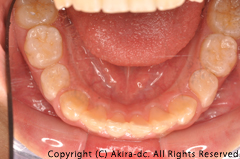

| 術前 下顎写真 | 術後 下顎写真 |